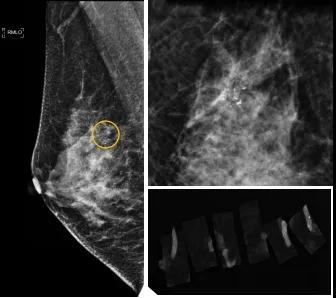

小到1—2mm的鈣化也能活檢!西安國際醫(yī)學(xué)中心醫(yī)院采用精準(zhǔn)技術(shù)讓乳腺早癌無處可逃

46歲的某女士在西安國際醫(yī)學(xué)中心醫(yī)院體檢時,行乳腺X線攝影(俗稱鉬靶)發(fā)現(xiàn)右乳可疑簇狀鈣化,分布范圍不到1厘米,臨床觸不到,超聲很難發(fā)現(xiàn),但是這種鈣化風(fēng)險比較高,依據(jù)國際BI-RADS指南需要明確病理!

西安國際醫(yī)學(xué)中心醫(yī)院影像診療中心陳寶瑩副主任帶領(lǐng)的團(tuán)隊,采用全數(shù)字化乳腺X線三維立體定位系統(tǒng)可實施。這個團(tuán)隊的成員大部分來自知名三甲醫(yī)院,有著十余年影像引導(dǎo)下乳腺介入診療的經(jīng)驗,X線引導(dǎo)穿刺定位和活檢例數(shù)居西北前列。為減少患者創(chuàng)傷,在詳細(xì)判讀了患者資料,并與患者及甲乳外科劉曉敏主任充分溝通的基礎(chǔ)上,團(tuán)隊確定采用全數(shù)字化乳腺X線三維立體定位系統(tǒng)下實施粗針活檢。

當(dāng)天,乳腺X線三維立體定位系統(tǒng)清晰顯示出了所有鈣化。為了獲取充足的組織量,保證病理診斷的準(zhǔn)確性,團(tuán)隊選用14G穿刺針并多點、多角度取材,組織取出后,又立即在高清標(biāo)本攝影系統(tǒng)中進(jìn)行投照,從而確定了取出組織中具有足夠的可疑鈣化。整個過程患者無任何不適,活檢結(jié)束后即回家觀察。

后期病理回報活檢組織條中均查見導(dǎo)管原位癌。該女士及家屬對西安國際醫(yī)學(xué)中心醫(yī)院早期發(fā)現(xiàn)并精準(zhǔn)確診病變的技術(shù)給予了高度的贊揚。

乳腺導(dǎo)管原位癌屬于早期的腫瘤性導(dǎo)管內(nèi)病變,有發(fā)展為浸潤性癌的傾向,需要早發(fā)現(xiàn)早治療,其預(yù)后明顯優(yōu)于浸潤性癌。2020年癌癥雜志的文章指出,近90%的導(dǎo)管原位癌僅表現(xiàn)為不可觸及的可疑鈣化,乳腺X線檢查是發(fā)現(xiàn)微小鈣化最敏感的方式,因此70–90%的導(dǎo)管原位癌是通過乳腺X線篩查發(fā)現(xiàn)。多年來國內(nèi)外指南,如美國國家綜合癌癥網(wǎng)絡(luò)(NCCN)指南及中國抗癌協(xié)會乳腺癌診治指南均建議40歲以上女性每年通過雙乳X線檢查(鉬靶)進(jìn)行乳腺癌篩查,高危人群建議提前進(jìn)行篩查(小于40歲)。由于雙乳X線篩查的推廣,歐美等國家導(dǎo)管原位癌的檢出率極大提高,明顯降低了乳腺癌的死亡率。在我國規(guī)范進(jìn)行乳腺X線篩查的人群比例比較低,很多人發(fā)現(xiàn)腫瘤時已經(jīng)為浸潤性癌,因此提醒大家高度重視規(guī)范的雙乳X線篩查。通過乳腺X線篩查發(fā)現(xiàn)的可疑鈣化需要在X線引導(dǎo)下精準(zhǔn)定位,進(jìn)行粗針穿刺或真空輔助旋切活檢,以獲得準(zhǔn)確的病理學(xué)結(jié)果,給予及時有效的治療。